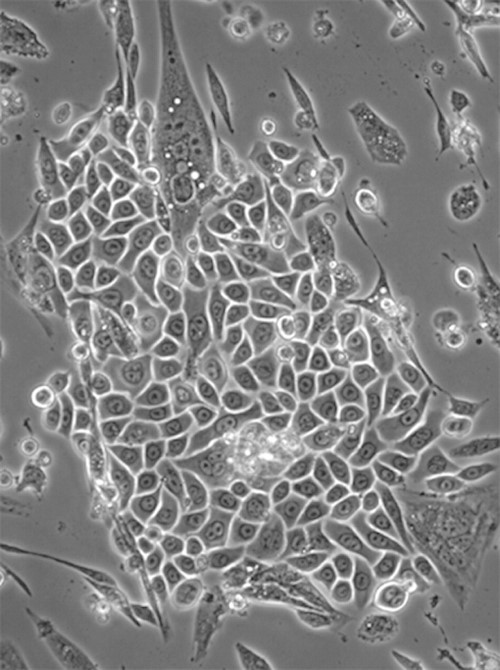

همونطور که قبل تر گفتیم؛ در محیط مرطوب فاکتور های رشد عملکرد بهتری دارند. حالا علاوه بر آن پانسمان مرطوب با نگه داشتن اگزودای حاوی فاکتور رشد GFs و پروتئین‏ های حیاتی در موضع زخم باعث تکثیر فیبروبلاست ها و سلول‏ های اندوتلیال و همچنین تکثیر و مهاجرت کراتینوسیت ‏ها می‏ شود.